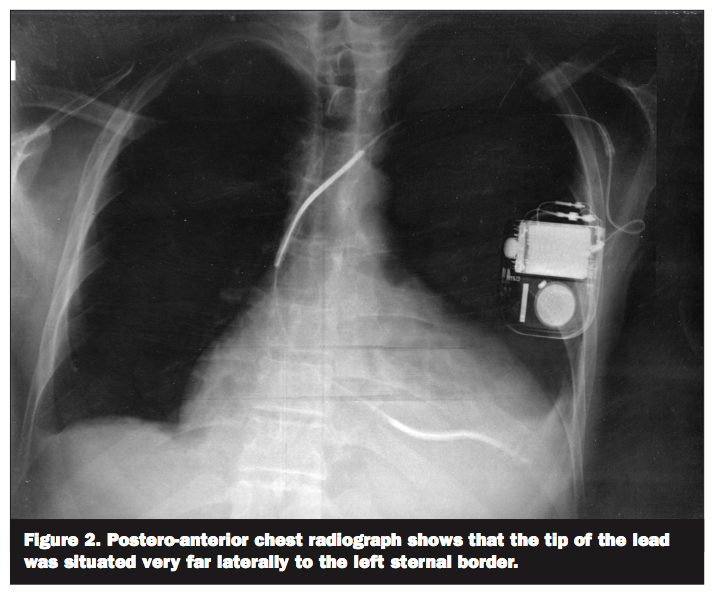

A 50-year-old male with congestive heart failure secondary to Ebstein’s anomaly presented for recurrent shocks from his implantable cardioverter-defibrillator (ICD). His electrocardiogram (ECG) (Figure 1) showed paced rhythm with right bundle branch block morphology which raised the question of left ventricular malposition of the ICD lead. On the postero-anterior chest radiograph (Figure 2) the tip of the lead was situated very far laterally to the left sternal border. A lateral chest

atrial or ventricular septal defects.1,2 It can cause thromboembolic events like stroke or peripheral arterial occlusion. This complication can be easily missed on intraoperative fluoroscopic imaging. ECG and chest radiographic findings often suggest the diagnosis. In proper positioning, the tip of the lead is expected to be adjacent to the left sternal border on the postero-anterior radiograph and to run anteriorly in the cardiac silhouette on the lateral radiograph. Definitive diagnosis can be established via echocardiography.